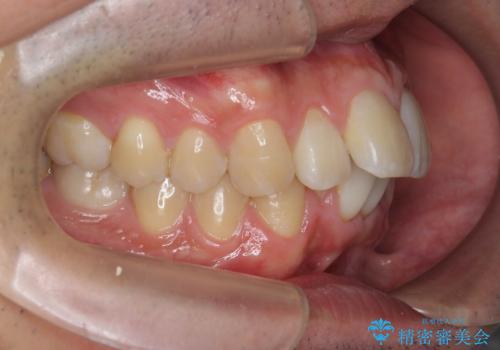

マウスピース矯正で前歯の角度、ガタガタをきれいに

- 突き出た前歯の角度、歯ブラシのしづらい前歯のがたつきの改善を希望され来院されました。

4本の小臼歯を抜きワイヤー矯正治療、下顎前歯を1本抜去しマウスピース治療のメリットデメリットを検討・相談し、より歯を抜く本数の少ないマウスピース矯正を行うこととなりました。

下顎の前歯は1本だけ抜去せざるをえませんでしたが、4本の小臼歯抜去とマルチブラケット矯正を回避することができ、治療結果・過程に満足いただくことができました。